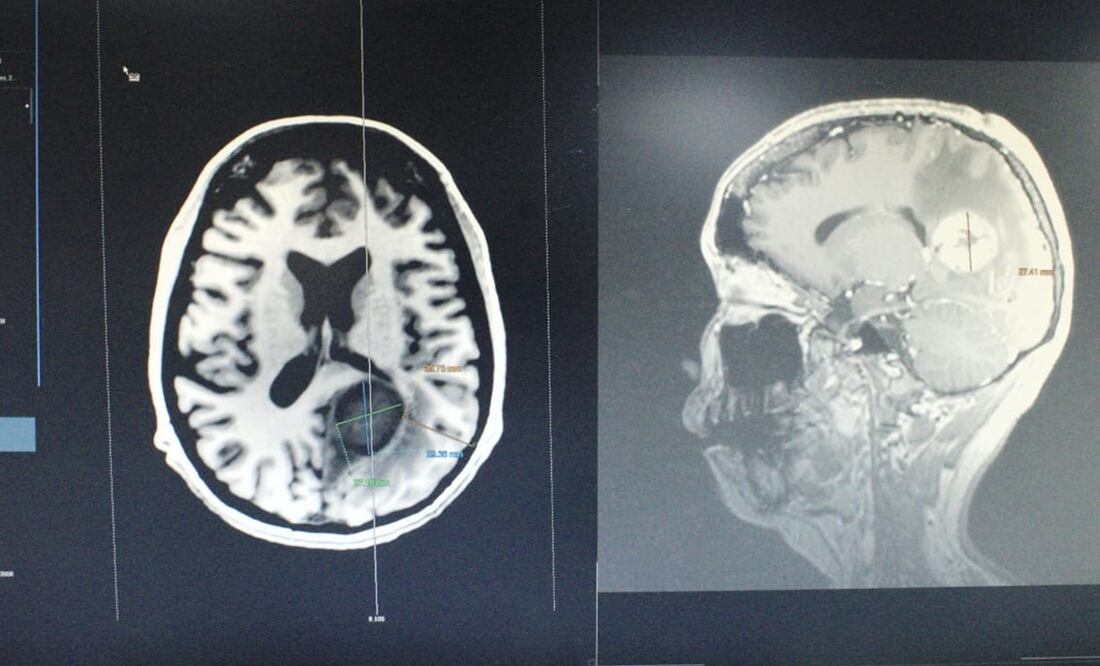

Un grupo multidisciplinario de médicos especialistas del Instituto de Seguridad y Servicios Sociales de los Trabajadores del Estado ( ISSSTE ) retiraron exitosamente un tumor cerebral maligno del tamaño de un huevo a una mujer de 34 años.

La operación se realizó en del Centro Médico Nacional (CMN) “20 de Noviembre”, duró cinco horas, y participaron cinco especialistas, un anestesiólogo y dos enfermeras especialistas, que lograron extirpar con éxito el tumor que se localizaba del lado izquierdo en la zona profunda del cerebro.

El diagnóstico de la paciente, cuya identidad no fue revelada, era una metástasis de cáncer tipo leiomiosarcoma desarrollado en el corazón. El tumor, informó el ISSSTE comprometía estructuras relacionadas con lenguaje, comprensión, cálculo y función visual.